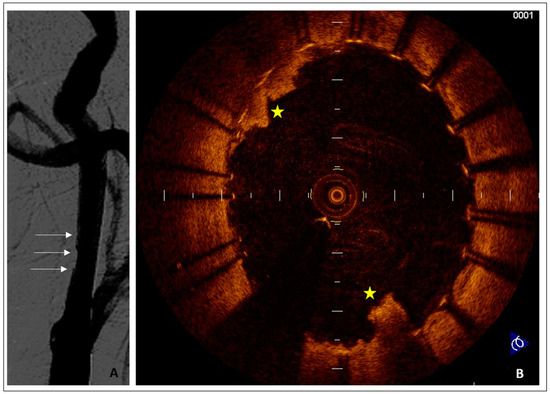

- Acute Carotid Stent thrombosis:

- Brief Case description:

- Plaque prolapse after carotid stenting

- Brief case description